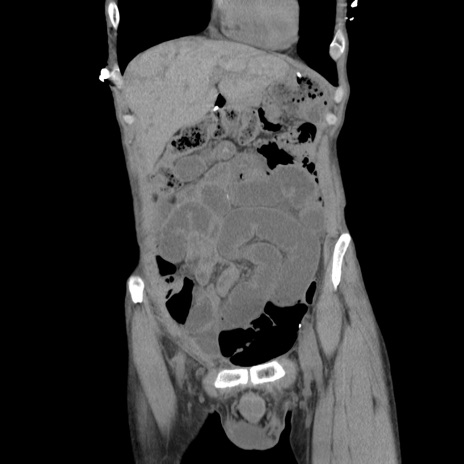

横断像

【症例】 60歳代男性

【主訴】 下腹部痛

【現病歴】 本日夜中より下腹部痛の症状認め、受診。

【既往歴】 膀胱癌(膀胱全摘+尿管皮膚瘻術) 、胃癌術後

【身体所見】 BT 35.3℃、PR 58/min、BP 136/98mHg、腹部平坦、軟、腸蠕動音±、ストマ留置あり、左上腹部~正中部に圧痛あり、反跳痛なし。

【データ】WBC 5100、CRP0.01